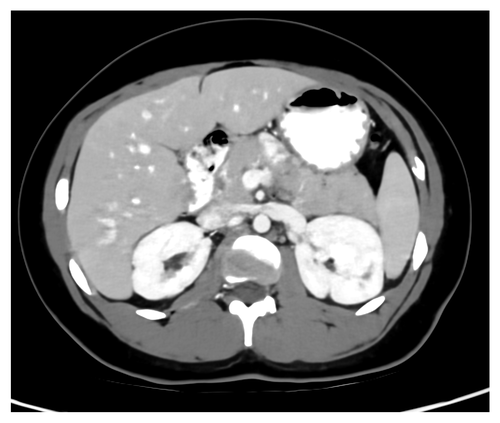

Fig. 9 and 10 show results for Exam 2, a low-contrast clinical exam. Both the full slice and zoomed views show that TMGAN produces a uniform texture for this low-contrast exam, while WGAN-VGG produces a uniform but coarser texture. More importantly, the arrows in Fig. 9(9) and 10(10) show that low-contrast features are best detected using the TMGAN-blended results.